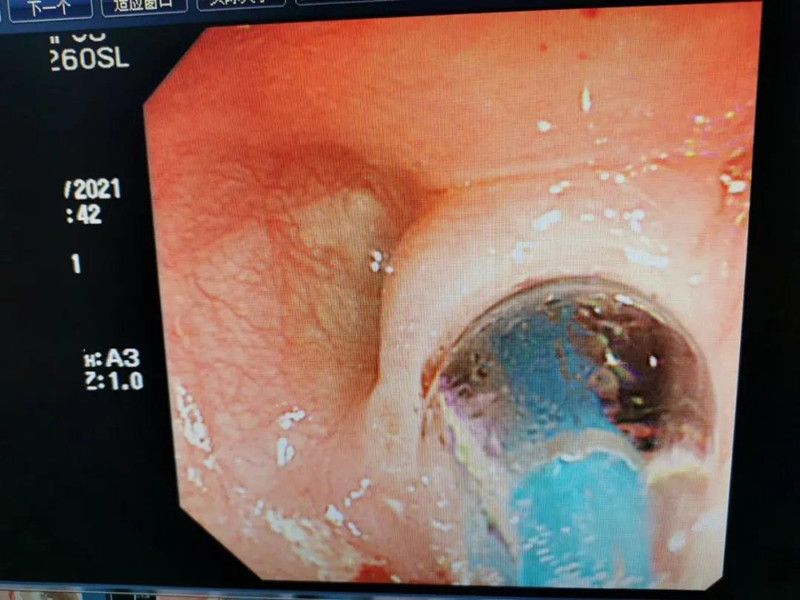

天天6个月了。最近总出现呛奶的情况,后来还出现肺炎症状。在蜜桃视频 经食道造影后,医生发现天天的症状是由术后并发症“食道吻合口狭窄”引起的,最窄处仅5mm多一点。食道狭窄球囊扩张术是目前最适合天天的手术了。内镜中心副主任边鹏说,这是一种微创介入治疗,具有创伤小、恢复快、合并症少的优势。2月26日,在麻醉科、内镜中心团队的合作下,边鹏为天天行经内镜下食道狭窄球囊扩张术。术中,边鹏用直径8mm的球囊进行扩张,将原来狭窄的食道扩成直径8mm的宽度。

天天太小,在球囊扩张的过程中,需要格外注意,不能扩张太快,否则会出现穿孔或大出血。所以边鹏每扩张3分钟,暂停3分钟,共扩张了3次。整个扩张过程很顺利,效果也非常好。次日,天天就出院了。在球囊扩张前,小儿内镜下显示,天天食道吻合口狭窄处上端竟有一团纸,家长也不清楚孩子是什么时候吃了纸。因为吻合口处太窄,纸下不去,形成了阻隔,导致天天最近总呛奶,奶汁进入气道,最终出现肺炎。